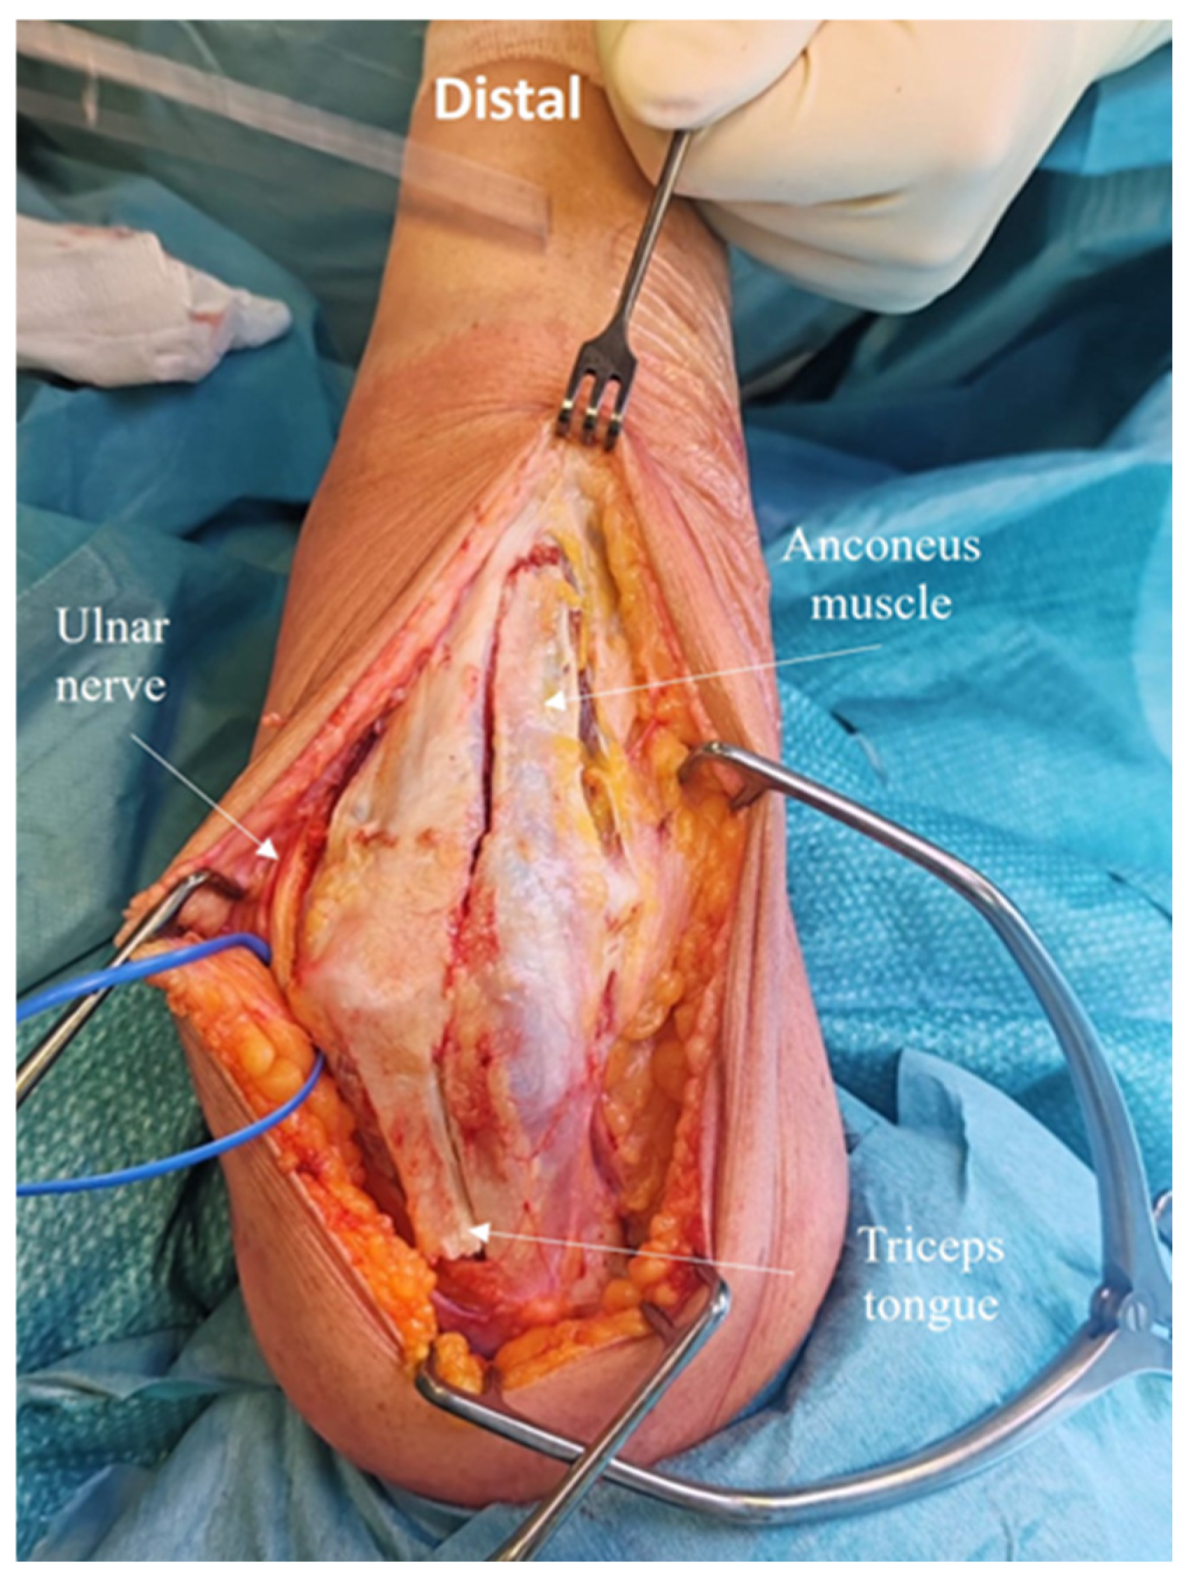

2.4. Development of the ARTT Approach